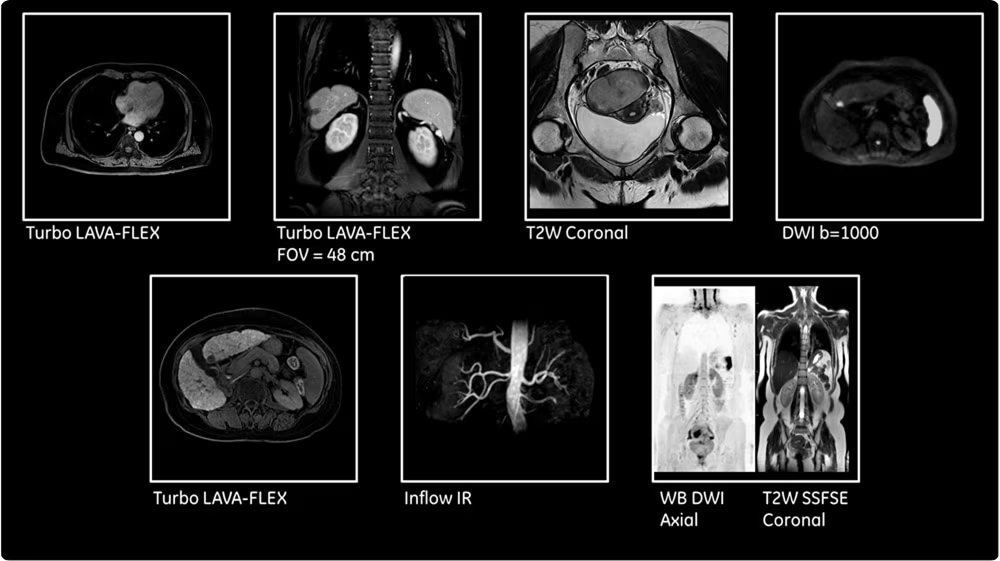

| МР-ангиография | Бесконтрастные и контрастные протоколы визуализации артериального и венозного русла различных анатомических областей. |

| Целотельные протоколы | Обследование всего тела для онкологического поиска, стадирования и мониторинга эффективности терапии. |

| Динамические контрастные исследования | Серийное сканирование после введения контрастного препарата для оценки васкуляризации и характеристик образований. |